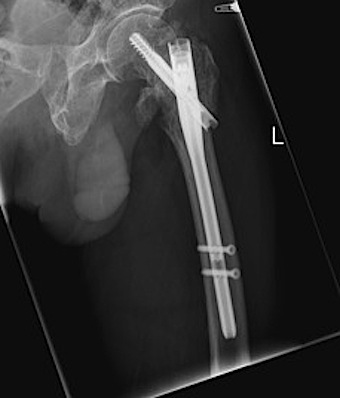

Sliding hip screw/dynamic hip screw

Cephalomdeullary nail

- Short / long

- one screw / two screws / blade

Cephalomedullary nail / Proximal femoral nail

Mechanical advantages

- load sharing rather than load bearing

- decreases lever arm

- supports medial cortex

Surgical advantages

- smaller incision / minimally invasive

- reduced blood loss

- shorter surgical times

Indications

- reverse oblique

- unstable fracture / loss of lateral buttress / loss posteromedial support

- subtrochanteric extension